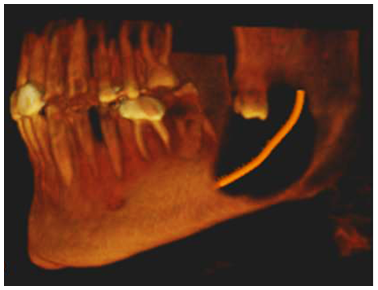

A CBCT was performed to identify the extension of the lesion and its relation with the IAC. Panoramic reconstruction (Figure 2A & 2B) shows a well-defined low density unilocular lesion circumscribing the crown of tooth #38 located vertically from the mid ramus extending below the level of the IAC, horizontally it extend from the apical third of the mesial root of #37 till the mid portion of the ascending ramus. Axial cuts (Figure 3) show expansion of the alveolar process and thinning and interruption of both lingual and buccal cortical plates. The roots of #37 show no resorption. The lesion is attached to tooth #38 at the level of the CEJ (Figure 4). The ectopic position of the IAC is also seen very clearly in the maximum intensity projection panoramic reconstruction (Figure 2B) and in the cross sectional images which shows the canal within the lesion (Figure 5A & 5B). After clinical and radiographic examination, a provisional diagnosis of dentigerous cyst was made; however, kerato cyst odontogenic tumor, amleloblastoma, ameloblastic fibroma were also considered in the differential diagnosis. Keratocyst don’t expand the bone to the same degree as presented here and attachment to the teeth will be more apically. Ameloblastic fibroma usually occurs in young patients which is not the case. Ameloblastoma would have presented internal septa if big in size as in this case. The most probable diagnosis is dentigerous cyst. The operation was performed under local anesthesia. Incision was made followed by raising a full thickness buccal mucoperiosteal flap. The lesion was then identified and the canal was viewed and confirmed, as seen on CBCT, to be passing in the center of the lesion. Dissection of the lesion away from the canal was performed using a tissue holder. With proper identification and isolation, the inferior nerve was preserved and the cyst was totally enucleated. Tooth number #38 was removed, and preservation of tooth #37. No sign of paresthesia was recorded after surgery. The surgical specimen was then sent for pathological analysis for final diagnosis. The histological examination showed a cystic lumen with blood content, a very thin lining of non-keratinized stratified squamous epithelium and dense fibro cellular connective tissue stroma with chronic inflammatory infiltrate. A macrophage and giant cell granuloma is noted around cholesterol crystals. There is no evidence of malignant change. The cyst opened measured 4x2x1 cm. A chronic inflamed dentigerous cyst was confirmed. Follow up CBCT was done after 3years of the surgery, and a progressive improvement in bone regeneration and healing process at the site of surgery was observed (Figure 6A & 6B); vitality test on tooth #37 response was positive.

Figure 5B 3D reconstruction showing the lesion and the position of the IAC.